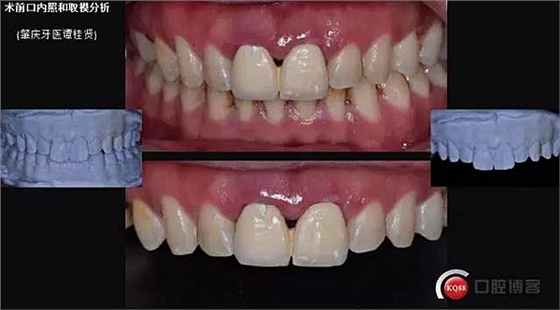

患者:32歲 男 要求重新修復(fù)前牙

主訴:上前牙咀嚼無力牙齦易出血,近日來烤瓷冠松動(dòng)脫落。

現(xiàn)病史:#11#21金屬烤瓷冠修復(fù)近十年了,近年來慢慢出現(xiàn)食物嵌塞不密貼,也非常影響美觀,但提起看牙醫(yī)便會(huì)驚出一身冷汗,近幾個(gè)月來牙冠慢慢出現(xiàn)松動(dòng),出現(xiàn)咬合痛,緊張的走進(jìn)了門診。

既往史:凝血功能稍差

口內(nèi)檢查:很輕易就取下牙冠,均為殘冠殘根且繼發(fā)齲,#21尤為嚴(yán)重,已到齦下,牙周探診1.5mm,X線檢查:根尖陰影,欠充。

診斷:#11#21殘根,繼發(fā)齲,輕度牙周炎。

一診口內(nèi)照

口外照